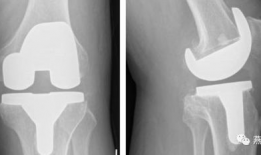

• 膝关节置换手术视频,从术前准备到术后康复

你有没有想过,当你的膝关节像老化的弹簧一样“嘎吱嘎吱”作响时,会有一种神奇的手术能把它换成一个全新的呢?没错,就是膝关节置换手术...